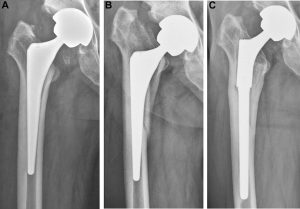

Femoral stem is designed in different sections or portions as neck, metaphyseal, and diaphyseal.

The neck portion is dedicating the femoral neck of the femur bone, while the metaphyseal and diaphyseal portions are designed to be anatomically matched with the anatomy of the proximal third bone at the trochanter and diaphyseal sections of the femur bone at the proximal third.

The design of the femoral stem in frontal plane would be managed with extended width at the proximal portion and narrowed gradually to the distal portion to be replaceable through the intramedullary canal of the diaphysis bone.

The extended width portion would be at the trochanter zone.

The basic principles of the femoral stem designing are similar among the all orthopedic implant manufacturers, however specific features and benefits design conceptions might be implemented to enhance its effectiveness in long-term implantation.